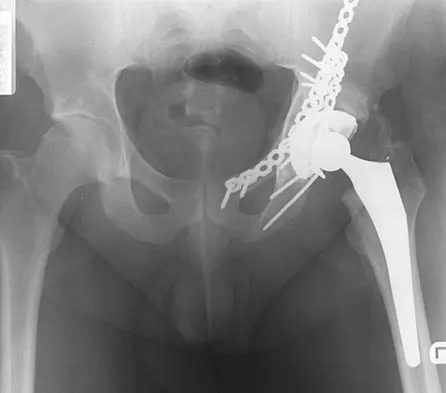

Figures 40a and 40b show the pre- and postoperative radiographs of an 82-year-old woman with bilateral hip pain who has had staged total hip arthroplasties. To minimize potential injury to the sciatic nerve at the time of surgery, the surgeon should

Explanation

To improve hip biomechanics and secure more suitable bone for acetabular fixation, the true acetabulum is often resurfaced in patients who have developmental dysplasia of the hip, thus lowering the hip center and lengthening the leg. Acute lengthening of more than 3 cm will place excessive tension on the sciatic nerve and require a femoral shortening to avoid sciatic nerve injury. The other maneuvers will not relieve sciatic nerve tension because of limb lengthening. Koval KJ (ed): Orthopaedic Knowledge Update 7. Rosemont, IL, American Academy of Orthopaedic Surgeons, 2002, pp 430-431.